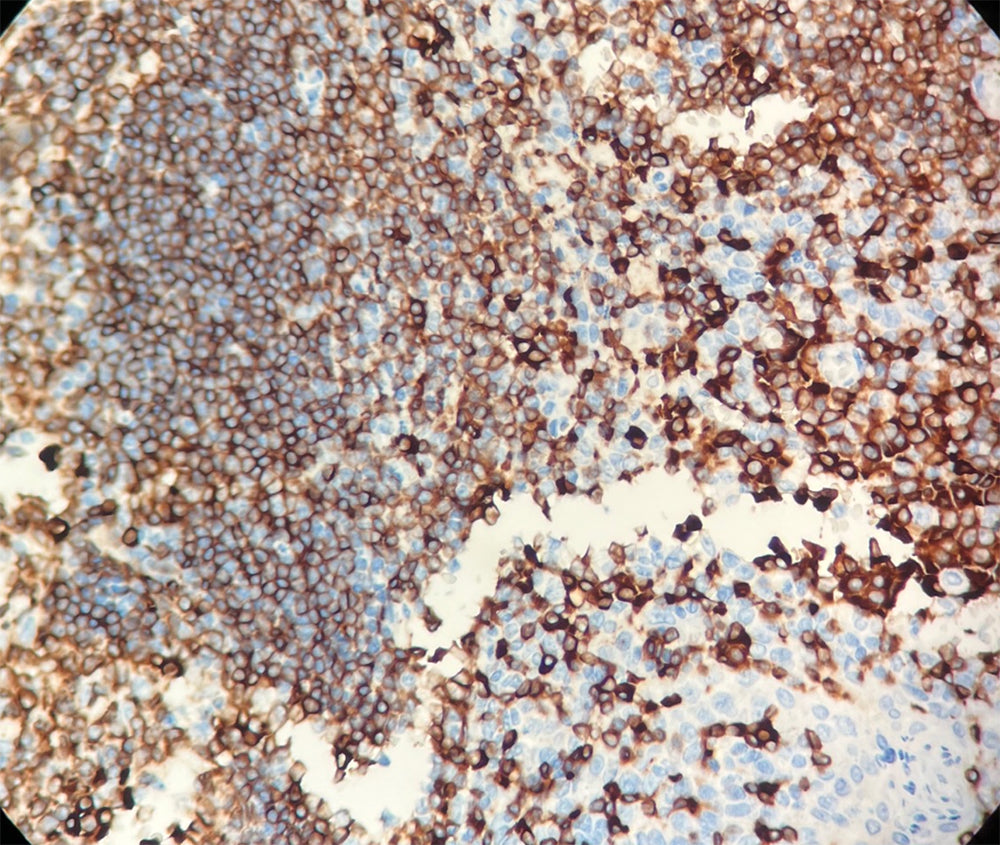

CD79a est un marqueur pan-B, spécifiquement exprimé sur les cellules B, dès le stade pré-B et persistant jusqu’au stade plasmocytaire (où il est présent sous forme intracellulaire).

CD79a est détecté dans la majorité des leucémies aiguës lymphoblastiques B, des cellules de la lignée B, des lymphomes B et de certains myélomes.

L’anticorps CD79a marque un spectre de lymphomes similaire à celui de CD20, tout en présentant une sensibilité supérieure dans les leucémies lymphoblastiques B précurseurs. Il montre également un taux de positivité plus élevé dans le myélome plasmocytaire et peut occasionnellement marquer certaines cellules endothéliales.

Il est à noter que CD79a est souvent positif dans la leucémie aiguë promyélocytaire (classification FAB-M3), mais rarement exprimé dans les autres leucémies myéloïdes.

Contrôle positif : Tissu amygdalien